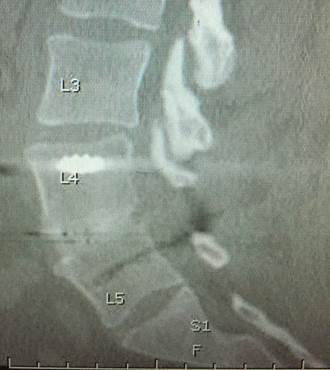

Solid Lumbar fusion at 6 months on CT scan with the EVOS-HA Lumbar Interbody System from Cutting Edge Spine.  Image courtesy of Timothy Bassett, MD.

During NASS, Timothy Bassett, MD, of SouthEastern Spine Specialists, Tuscaloosa, AL, presented his ‘Early Clinical Experience with a PEEK-OPTIMA HA Enhanced Device for Lumbar Fusion’. The 1-2 level TLIF (Transforaminal Lumbar Interbody Fusion) procedure utilised the EVOS HA Device, from Cutting Edge Spine, intended for use in skeletally mature patients with Degenerative Disc Disease (DDD) of the lumbar spine, plus autograft bone with posterior instrumentation. No biologics were used in this series of nine patients.

The clinical results were evaluated for pain on the Visual Analogue Scale (VAS), opiate usage, neurological function, re-operations and complications. Fusion results were evaluated using anteroposterior (AP) and lateral X-rays at six weeks and 12 weeks, and a CT scan at six months. Dr Bassett concluded, “Very rapid visible bone fusion occurred in the interbody region in six weeks, according to plain radiographs, with correspondingly good clinical results including no neurologic consequences beyond 6 weeks, no implant migrations, no subsidence, and no pseudoarthroses. More importantly, 9/10 fusions were definitively solid on 6 month CT scan with autograft bone, despite some challenging patients.  The one that didn’t show complete fusion was progressing to fusion and used one pack of tobacco daily, both pre- and post-operative, contributing to the fusion challenge.